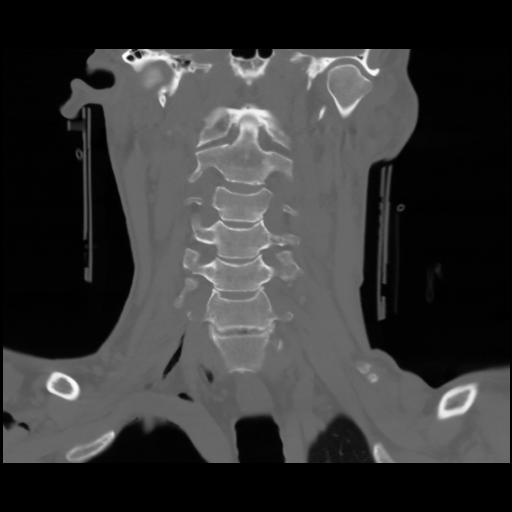

13 P.BLANDAS,,Coronal,2.000,P.BLANDAS,Coronal,